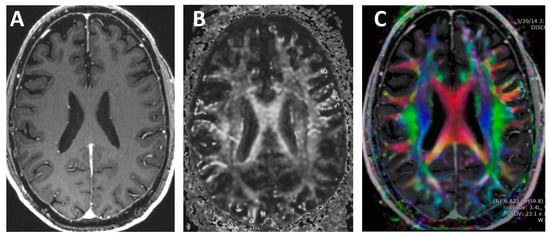

Conventional MRI imaging techniques do not provide information on the direction of the white matter tracts. In contrast, DTI quantifies both the asymmetry and the amount of water diffusion and displays this information on color-coded maps [,,,,,,,,,], see Figure 8. The concept of diffusion can be thought of as an ink drop falling onto a piece of wood. The rate of growth will be fastest in the direction along with the grains of the wood. Likewise, water diffusion is axons is directionally dependent.

Figure 8.

T1-weighted and diffusion tensor imaging (DTI). (A) Contrast-enhanced T1-weighted image. Note that the white matter is all the exact same grayscale and the direction of each white matter tract cannot be discerned. (B) Grayscale DTI anisotropy map for one diffusion-sensitizing gradient. Note that there are varying grayscales within the white matter, which correspond to the amount of diffusion signal for the particular directional diffusion-sensitizing gradient applied during the acquisition. (C) Color DTI anisotropy map overlaid onto a T1 post-contrast image. The Color DTI anisotropy is based on the composite of multiple diffusion-sensitizing gradient images. Note that there are multiple colors within the white matter map with red indicating transverse direction, blue indicating superior–inferior direction and green indicating anterior-posterior direction.

The DTI sequence is a spin-echo diffusion-weighted pulse sequence with diffusion weighting in multiple different spatial directions using diffusion-sensitizing gradients. A typical DTI protocol will have a typical slice thickness of 2 mm and matrix of 128 × 128 [,,]. For each diffusion-sensitizing gradient, the 4D dataset includes x, y, z spatial locations with a diffusion constant proportional to the magnitude of diffusion. A minimum of six diffusion-sensitizing gradients are used; however, modern protocols typically include 30 directions [].

Two important DTI metrics include fraction anisotropy (FA), which is a measure of the asymmetry of diffusion and mean diffusivity, which is a measure of the magnitude of diffusion []. Formulas for FA and mean diffusivity (MD) are shown in Figure 9. Normal white matter is highly anisotropic and has high FA and low MD; however, during traumatic axonal injury, white matter FA and MD can be altered.

One of the technical limitations that many researchers are attempting to overcome is the ability to assess intravoxel fiber tract crossing [,,,,]. Some of the newer DTI techniques including diffusion kurtosis imaging (DKI), Q-ball, neurite orientation dispersion and density imaging (NODDI), and Diffusion Spectrum Imaging (DSI) attempt to overcome these limitations [,,,,,,,,,,,], see Figure 10. If a more thorough review of DTI techniques is desired, we would like to refer readers to one of our prior manuscripts that discusses DTI in greater depth [].

Figure 10.

Example of Q-ball imaging (QBI). (A) QBI type DTI with color anisotropy map full field of view. (B) Zoomed in region from the white rectangle in (A) with probability distributions in each voxel superimposed on a grayscale FA map. QBI acquisition parameters: 112 × 112 matrix; 22.4 × 22.4 cm field-of-view; 70 axial slices of 2 mm thickness; 6 b.0 images; 60 gradient directions at b.2500 s/mm2; SENSE acceleration factor 2; TE/TR.107 ms/10.3 s; and, acquisition time 11 m 20 s.